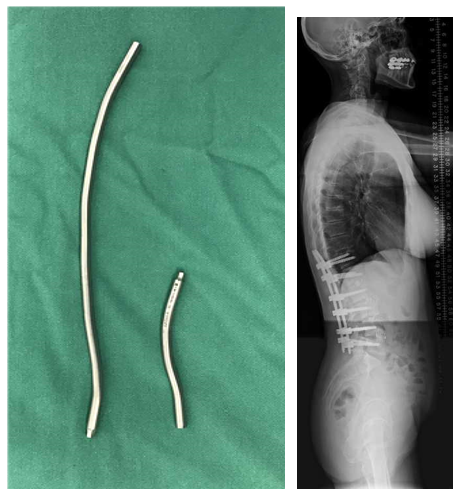

3.降低内固定硬度和减少融合区内固定数量

(1)降低内固定棒的硬度,用钛合金代替钴铬合金棒;

(2)全节段椎弓根螺钉固定改用间隔置钉固定;

(3)适当降低固定融合区内固定强度。

图25 降低内固定硬度和减少融合区内固定数量